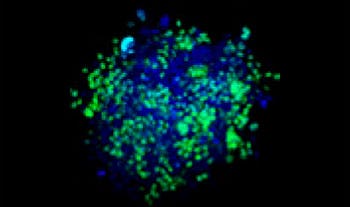

Making the spheroids transparent and imaging them with an FV3000 confocal laser scanning microscope enabled us to image the co-cultured cancer spheroids at depth. Staurosporine treatment increased the number of dead cells in a dose-dependent manner (Fig. 2*1). Three-dimensional analysis is required to determine which cells are dead and how many dead cells there are in a three-dimensional mass.

Figure 2. Drug response in co-culture spheroids

Figure 2. Drug response in co-culture spheroids*1

The Hoechst33342 signals enabled us to recognize the nuclei. All cells were classified into two groups based on the presence or absence of an EGFP signal—EGFP positive (HeLa cells) and EGFP negative (A549 cells). The cells in these two groups were further divided according to the presence or absence of dead cell signals (TO-PRO3, red) for a total of four groups (Fig. 3*1). The percentage of live to total cells of both A549 and HeLa cells was calculated and plotted (Fig. 4). The results showed that HeLa cells were more sensitive to staurosporine than A549 cells.